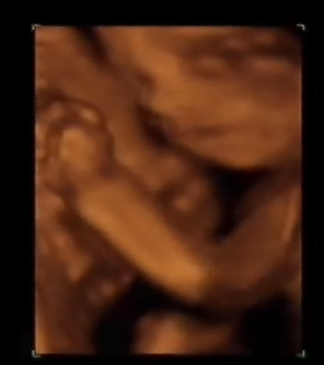

Es el mismo feto que el anterior y observen con que calidad se ven las piernas y pies. Es también un momento excelente para observar el sexo del feto.